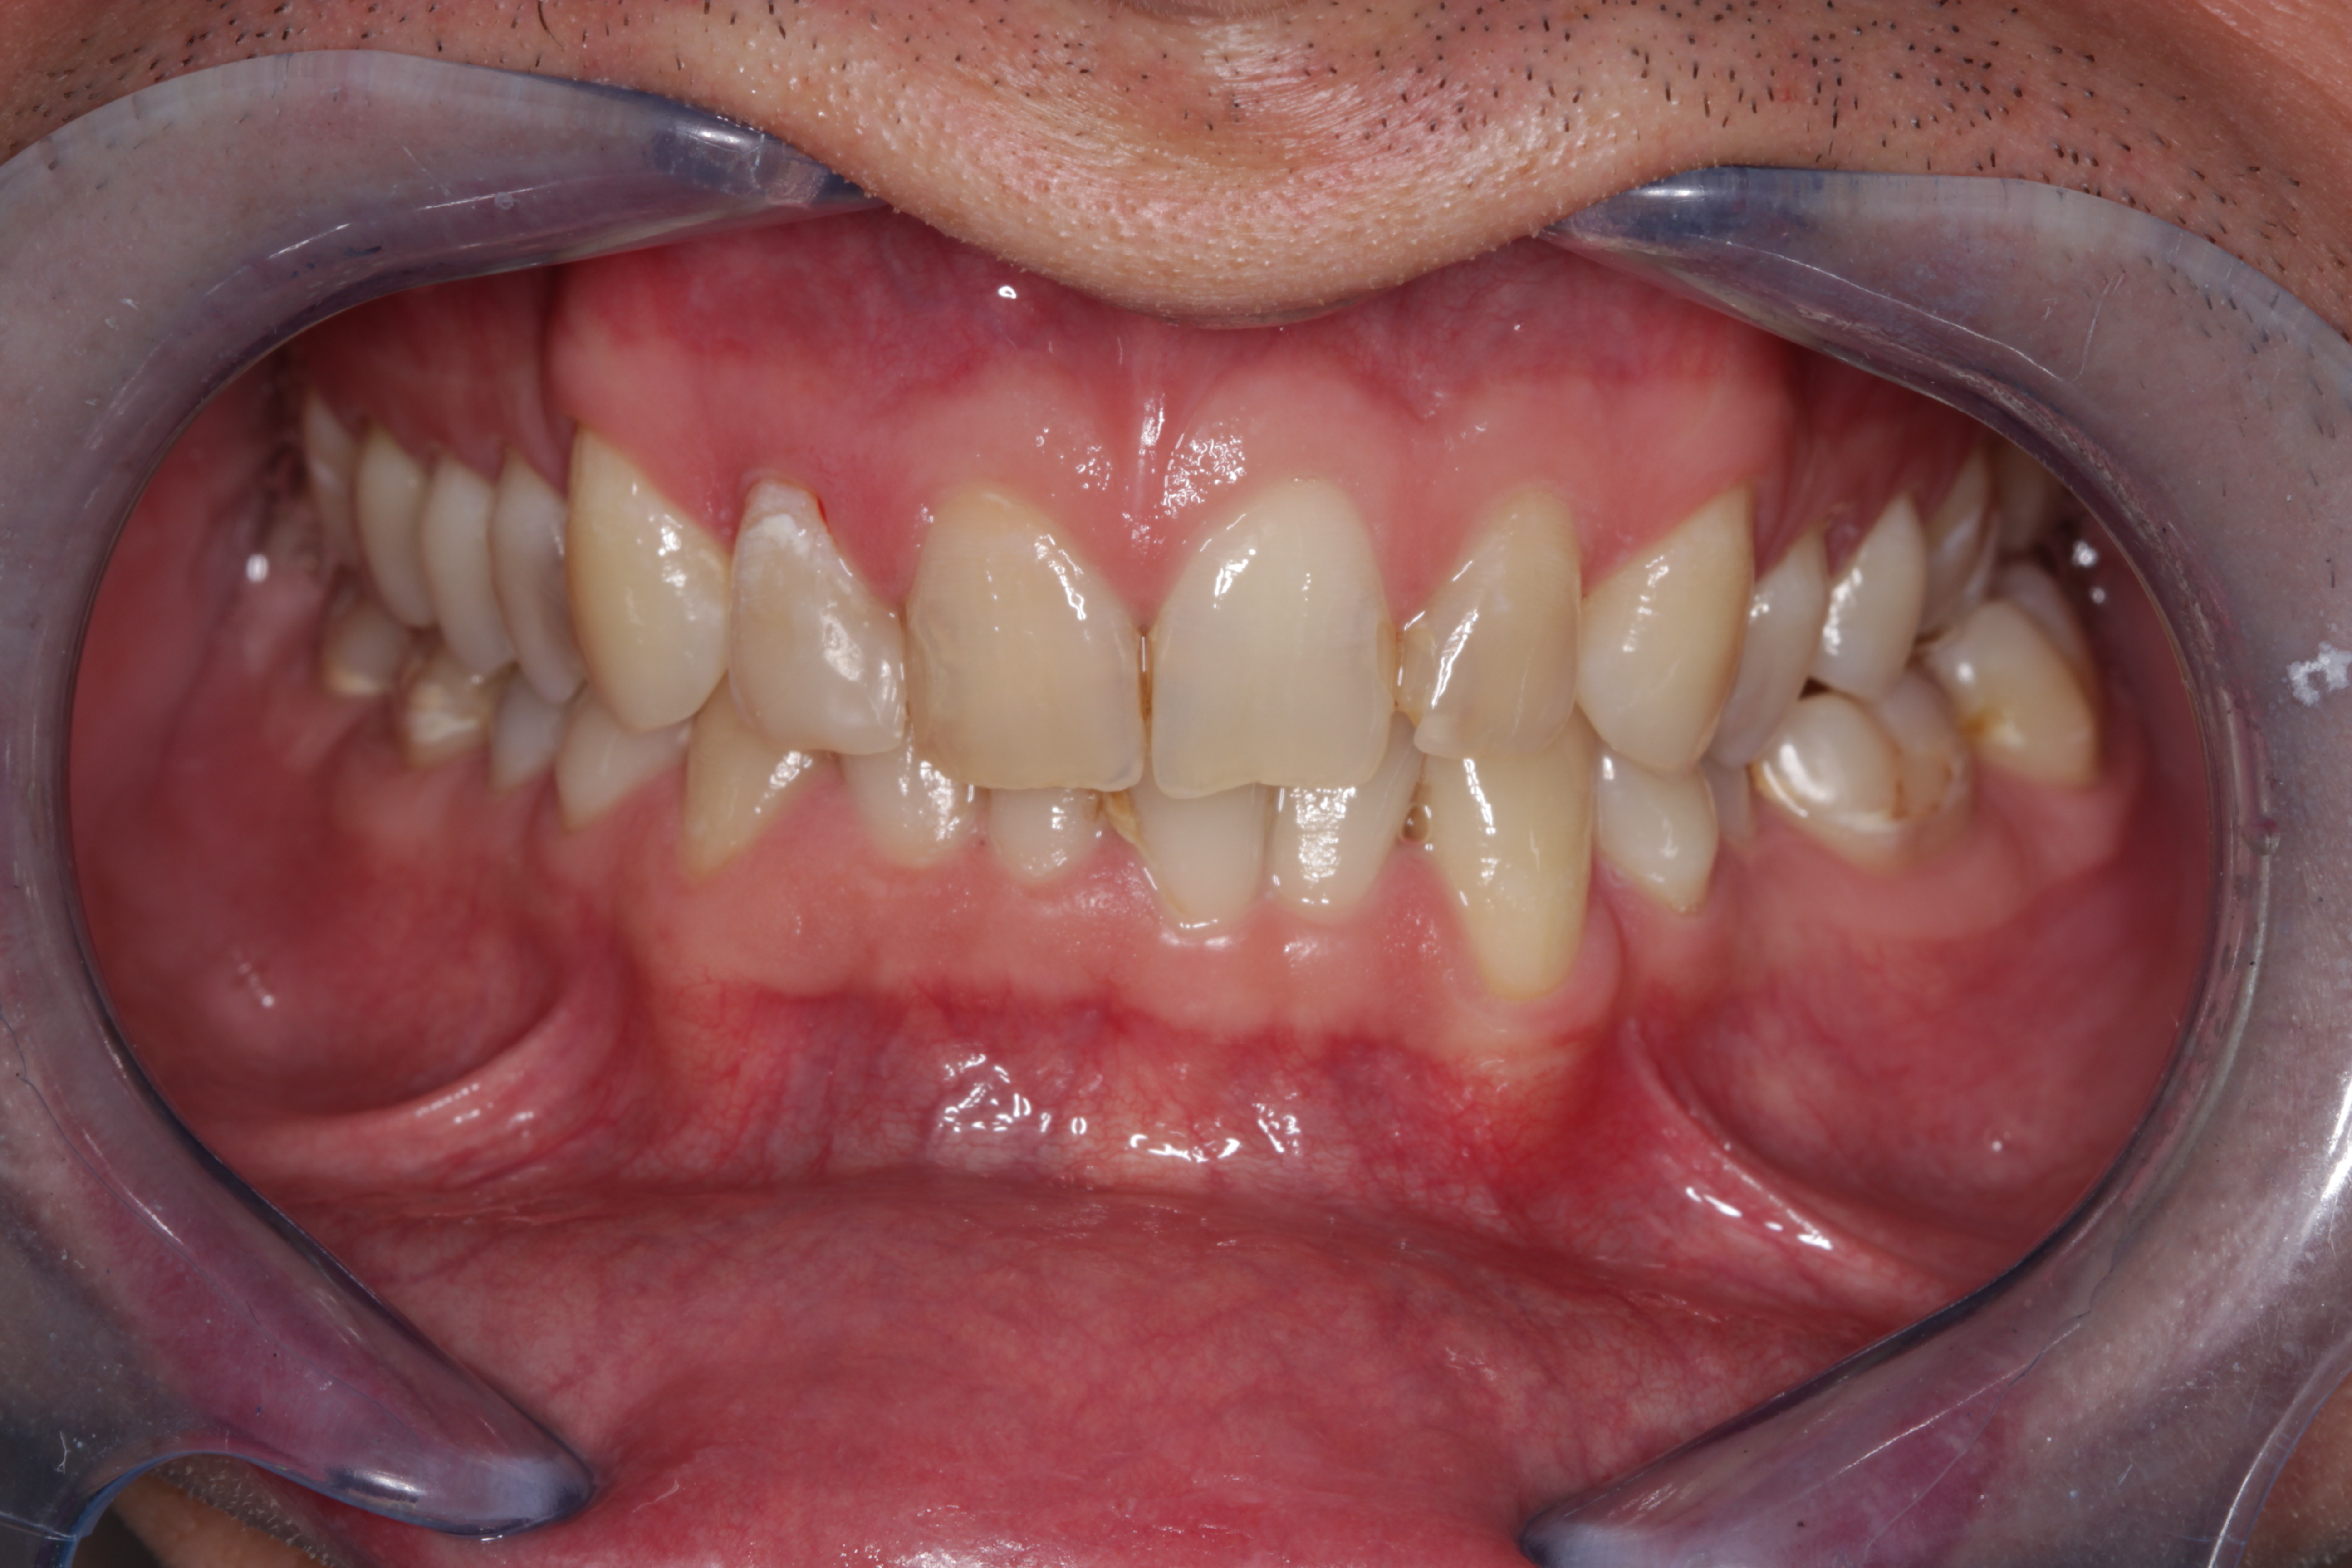

- Rehabilitación postraumática